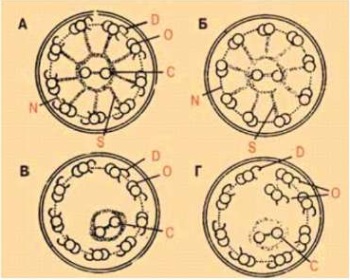

Первичная цилиарная дискинезия (ПЦД) — орфанное заболевание (MIM 244400), чаще всего с аутосомно-рецессивным типом наследования, характеризующееся дисфункцией подвижных ресничек. Основными проявлениями ПЦД являются хронические заболевания верхних и нижних дыхательных путей, аномалии расположения органов, которые встречаются примерно у 50% пациентов с ПЦД (синдром Картагенера), врожденные пороки сердца, также характерно бесплодие у мужчин и склонность к внематочным беременностям у женщин.

Цель обзора — представить данные о современных методах диагностики ПЦД, которые возможны в Российской Федерации. Диагностика ПЦД является сложной задачей, так как нет единого «золотого стандарта», позволяющего полностью установить или исключить заболевание. Для точного определения ПЦД необходимо проводить ряд специализированных исследований, которые основываются на сочетании клинических данных, генетического анализа, а также анализа ультраструктуры и функции реснитчатого эпителия. Дополнительные тесты включают уровень оксида азота в выдыхаемом воздухе и повторные тесты в образцах культур ресничек. Педиатры, неонатологи, пульмонологи и оториноларингологи должны поддерживать высокую осведомленность о ПЦД и направлять пациентов в специализированные центры для подтверждения диагноза.